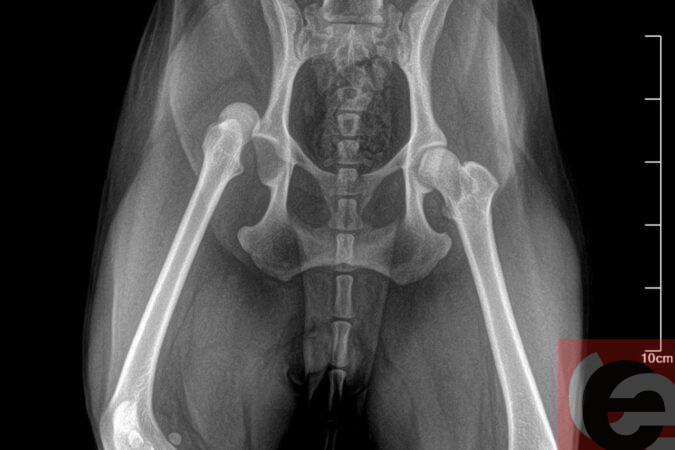

- В ветклинике мне сказали, что нарушилось кровообращение в лапе, поэтому Ника не может самостоятельно ходить. Хотя когда конечности "затекают", это быстро проходит. На следующий день я вновь повела Нику в клинику. Хирург сделал рентген и поставил диагноз - "вывих тазобедренного сустава", - поделилась обеспокоенная сибирячка.

Фото: читатель "Прецедента"